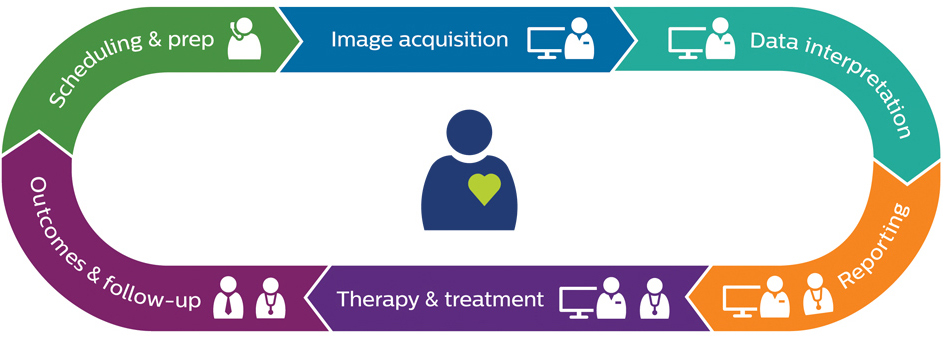

Key capabilities to optimize your radiology workflow

Explore our end-to-end vendor-neutral solutions that leverage AI7 to simplify and efficiently connect workflows across the imaging enterprise to help reduce variability and staff workload, increase productivity and enhance the patient experience.

Scheduling and preparation

Inform, educate, engage and comfort patients throughout the care journey with personalized tools.

Image acquisition

Promote efficiency and confidence in image acquisition with smart systems and smart workflows.

Image and data interpretation

AI-driven platforms for workflow orchestration, data access, advanced analysis, reporting and clinical collaboration.

Reporting and results communication

Integrated, AI-driven enterprise scalable platforms for smart reading and reporting.

Outcomes and follow-up care

Tools and data insights for continuous performance improvement.